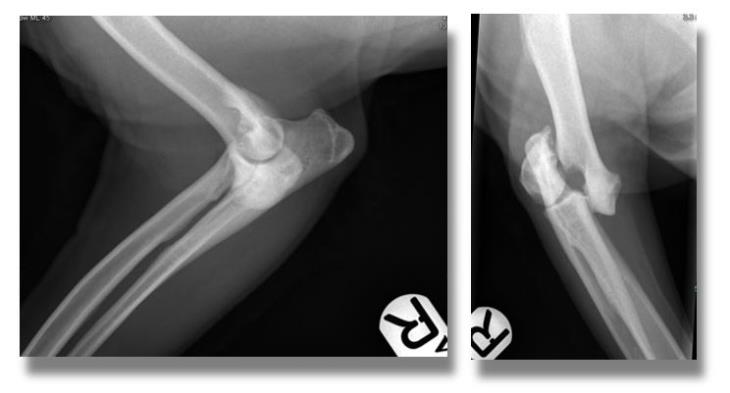

An 8-year-old male Cocker Spaniel was presented to Eastcott Referrals after having been diagnosed with a traumatic fracture of his right humerus by his local vets.

His radiographs had shown a displaced fracture of the lateral part of the right humeral condyle.

This represents a fracture involving the elbow joint and it requires careful surgical repair in order to restore limb function and prevent the onset of severe osteoarthritis.

A CT scan of the affected limb was obtained to allow for preoperative planning and to rule out additional fissures that might have gone undetected on plain radiography.